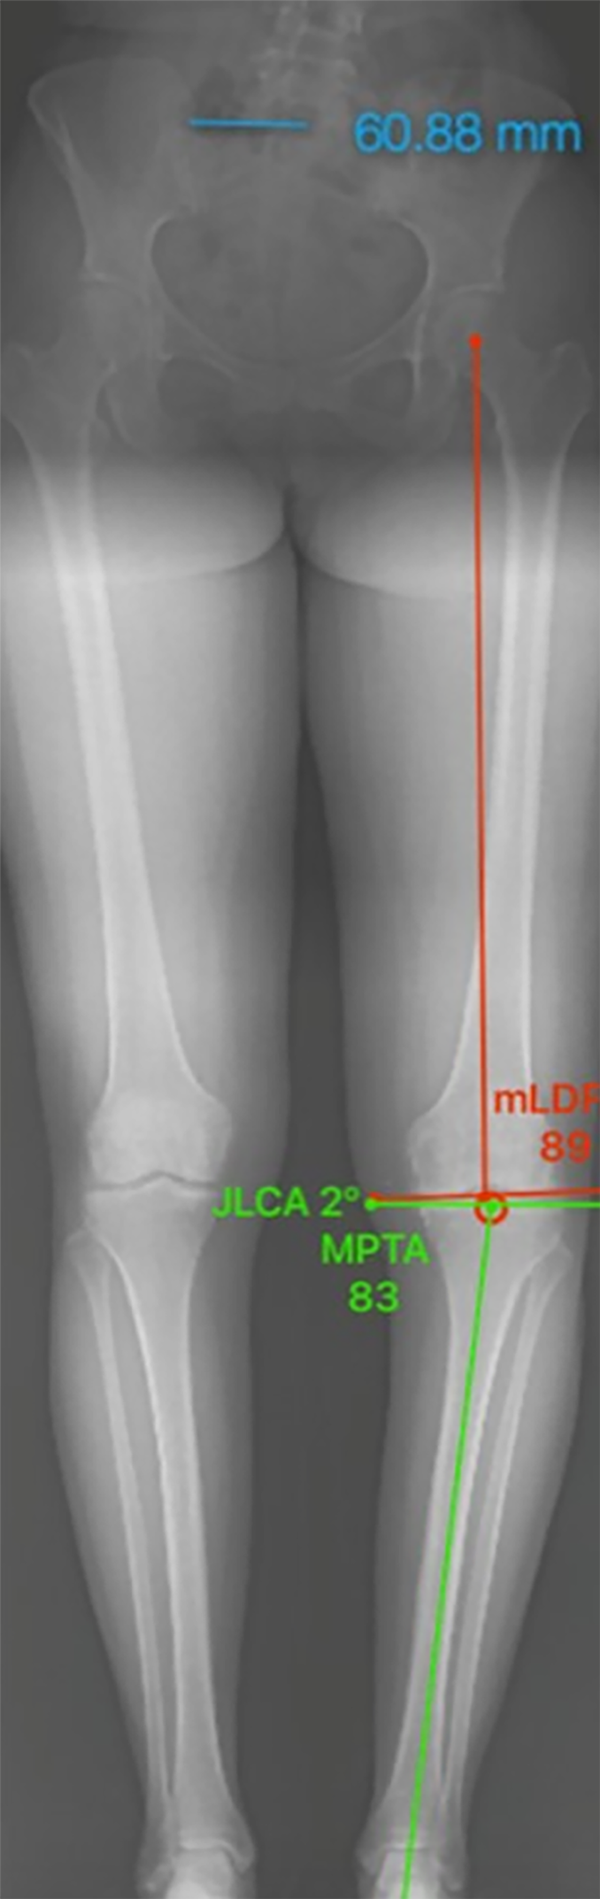

Determinar el punto de corrección. Trazar una línea desde el centro de la cadera y el centro del tobillo dirigidos a este punto, la intersección de estas líneas son el grado de corrección. Punto de corrección: ancho de tibia 73 mm (62%: 45 mm), 10° de corrección.

Figura 26: Imagen correspondiente al Paso 3.